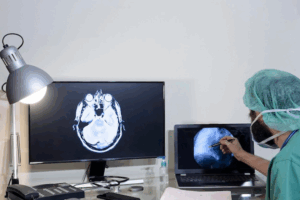

What is an MRI Scan? MRI scans are a type of safe, non-invasive imaging test. MRI stands for Magnetic Resonance Imaging. Doctors use MRI scans

What is a CT Scan? A CT scan, or computed tomography scan, is a special type of X-ray. It takes many pictures of your body